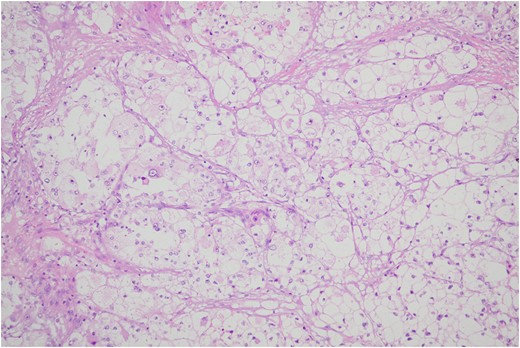

Histologic sections of the mass show distinct variably sized and shaped collections of uniform polygonal tumor cells, separated by fibrovascular septa and delicate capillary-sized vascular channels lined by flattened endothelium at low magnification (Fig. 5). Within the tumor nests, there is loss of cellular cohesion and necrosis of the centrally located cells in the nests results in the pseudo-alveolar pattern (Fig. 6). Vascular invasion is also present (Fig. 7). The individual tumor cells have distinct cell borders and abundant eosinophilic to clear, somewhat granular cytoplasm surrounding a central nucleus with variably sized nucleolus. Nuclear atypia is rarely seen. Mitotic figures are uncommon. The cells contain rhomboid or rod-shaped crystalline inclusions that are faintly apparent on routine histology and are better demonstrated with periodic acid-Schiff stain after diastase digestion (Fig. 8).

Crystalline inclusions demonstrated with periodic acid-Schiff stain after diastase digestion.